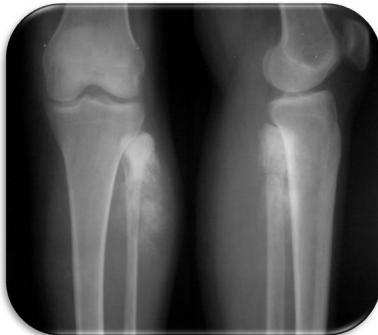

site: distal femur size: Most (involving how much? / cm?) matrix: mixed - mainly radiopaque , wide zone of transition, cortical destruction, resulted periosteal reaction, and codman’s triangle soft tissue involvement: